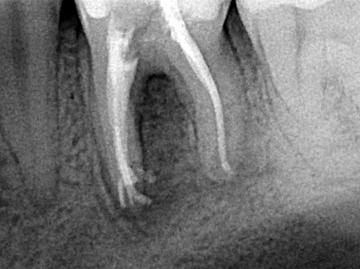

Każdy ząb zbudowany jest z zębiny i szkliwa, czyli substancji tworzących rdzeń zęba oraz miazgi, która odżywia i unerwia ząb. Niestety drobnoustroje bytujące w ubytkach zębów prowadzą do nieodwracalnych stanów zapalnych miazgi zęba, które skutkują koniecznością leczenia kanałowego. Generalnie zabieg polega na usunięcia zainfekowanej miazgi, poszerzenia światła kanałów i ich dokładnego wypełnienia. Dzięki tej popularnej metodzie możemy zachować zęba w jamie ustnej na dalsze lata. Jednak ze względu na brak odżywania, zęby leczone kanałowo są kruche i podatne na złamania. W związku z tym wymagają odpowiedniego zabezpieczenia aby służyły przez kolejne lata. Najpopularniejszą metodą to pokrycie zęba kosmetyczą koroną porcelanową.